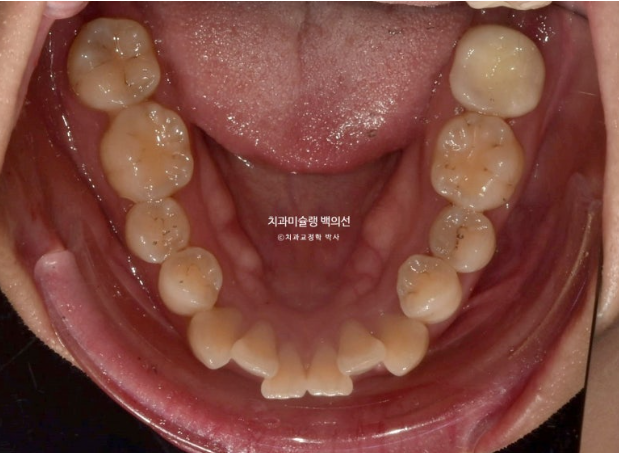

23년 10월 교정을 위해 온 30대 환자분입니다.

앞니는 뻗쳐있고 좌측 큰어금니 자리가 비어있습니다.

아래 앞니는 삐뚤하여 배열할 공간이 필요하고

위 첫번째 큰어금니 (제1대추치)가 한쪽은 발치되어있고 한쪽은 아직 발치는 안 했지만 발치진단이 나온 상황입니다.

상악은 빼야하는 제 1대구치 (첫번째 큰어금니) 두 개를 빼고 공간을 없애면서 앞니를 뒤로 보내고 사랑니 큰어금니 자리로 데려와 대체하여 쓰기로 합니다.

이렇게 하면 큰어금니 자리를 임플란트 없이 교정으로 마무리가 가능하니 일석이조 입니다

하악은 양쪽 사랑니를 빼고 사랑니 공간으로 후방이동 시켜 앞니를 뒤로 보내기로 합니다.